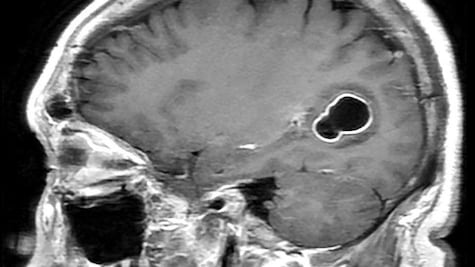

La compañía emergente, cofundada por Musk en 2016, pretende desarrollar un canal de comunicación directa entre el cerebro y las computadoras, con el fin de, en una fase inicial, devolver la autonomía a personas con necesidades médicas

El chip fue entrenado con un método de inteligencia artificial llamado red neuronal, que decodifica palabras según la actividad cerebral que se produce cuando intenta articularlas

Con lo anterior, Noland Arbaugh se convierte en el primer ser humano en usar el implante cerebral para controlar el cursor o el teclado de un computadora utilizando únicamente sus pensamientos